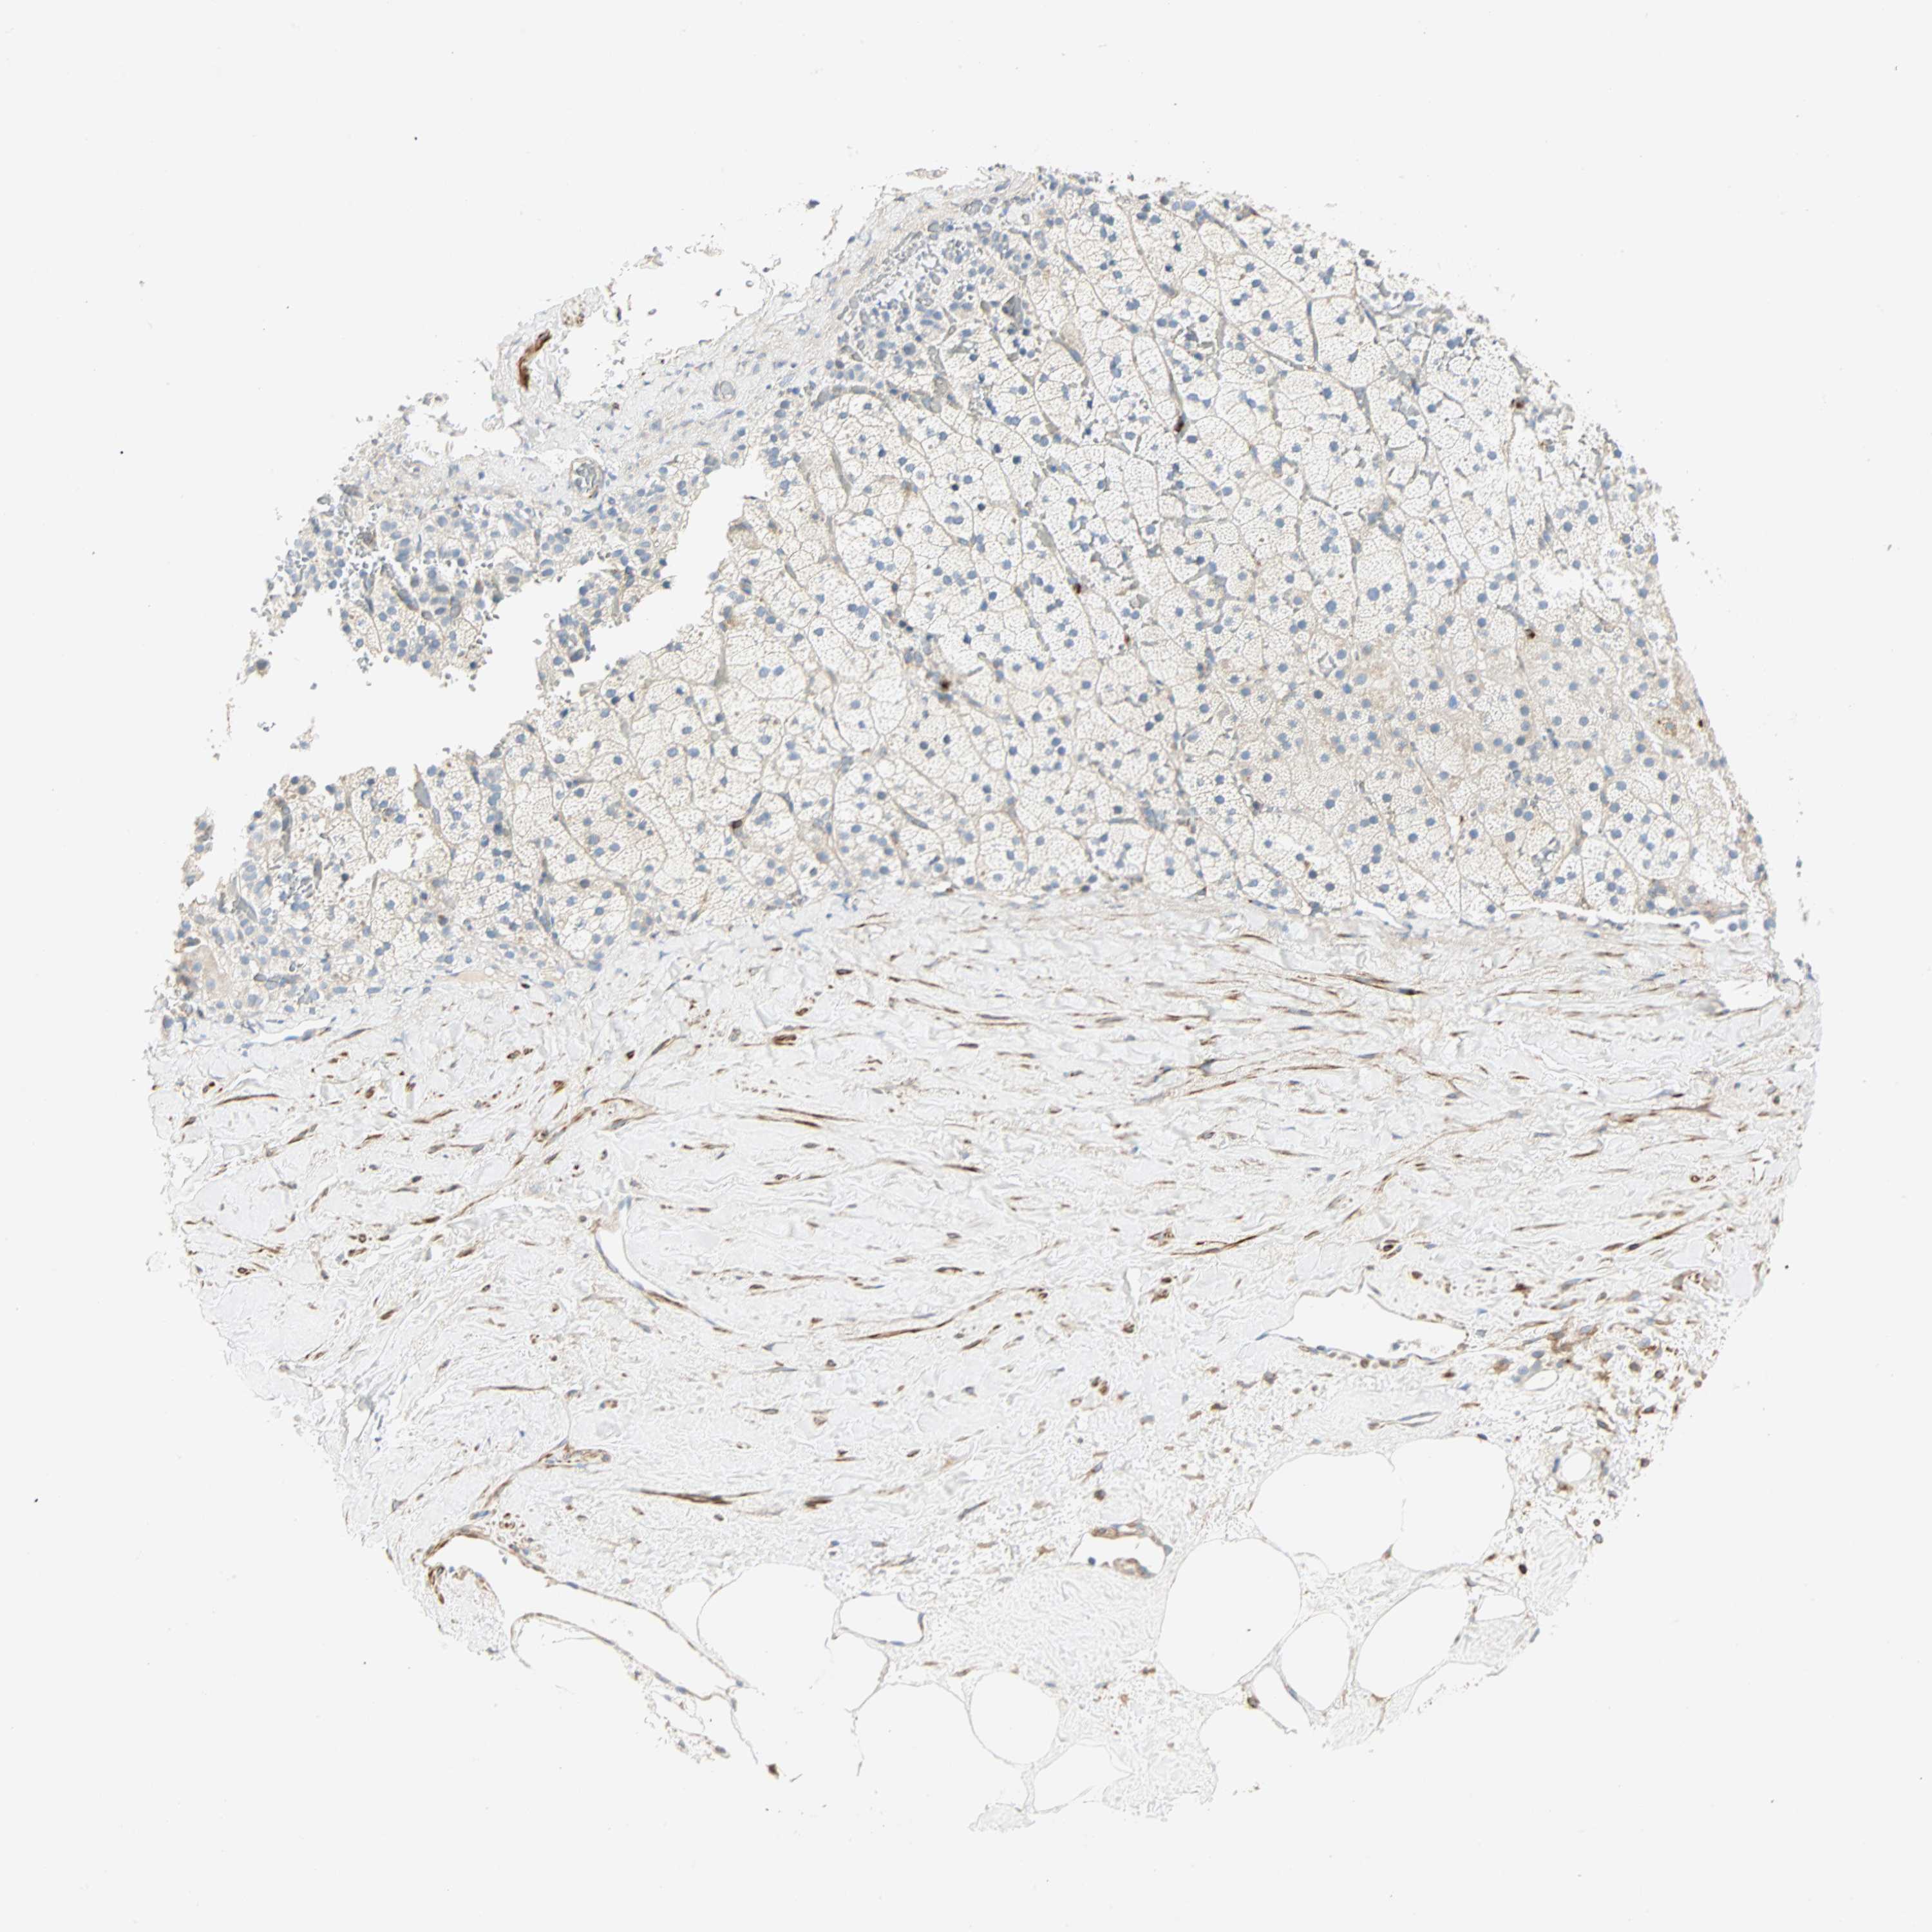

ADRENAL GLAND - Antibody stainingi

Antibody staining in the annotated cell types in the current human tissue is reported as not detected, low, medium, or high, based on conventional immunohistochemistry profiling in selected tissues. This score is based on the combination of the staining intensity and fraction of stained cells.

Each image is clickable and will lead to virtual microscopy that enables deeper exploration of all samples and also displays staining intensity scores, fraction scores and subcellular localization as well as patient and tissue information for each sample.

Antibody HPA008129Antibody HPA028288

Glandular cells Not detectedNot detected